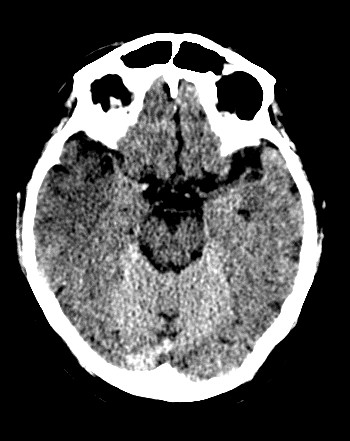

CASO 2:

Paciente con alteraciones del habla y disminución de la fuerza del brazo izquierdo. Ictus previo hace 4 años.

ASPECTS: Territorio M1 + Lenticular derecho = 10 – 2 = 8 puntos.